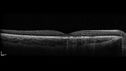

11 year old male When school started the patient noticed that he was having trouble reading and seeing out of both eyes. There are no retinal diseases in the family.

VA OD: sc20/25

VA OS: sc20/40

TP: OD:19 OS:18